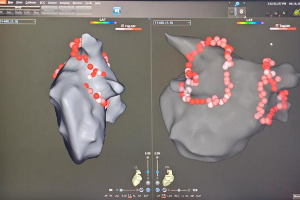

6月18日,玉溪市人民医院心内科成功为一位既往有房间隔缺损并接受过房间隔封堵术的房颤患者,完成了高难度的心房颤动射频消融手术。这一手术的成功,不仅体现了医院心内科在复杂心血管疾病治疗领域的卓越实力,更为广大房颤患者带来了新的希望。